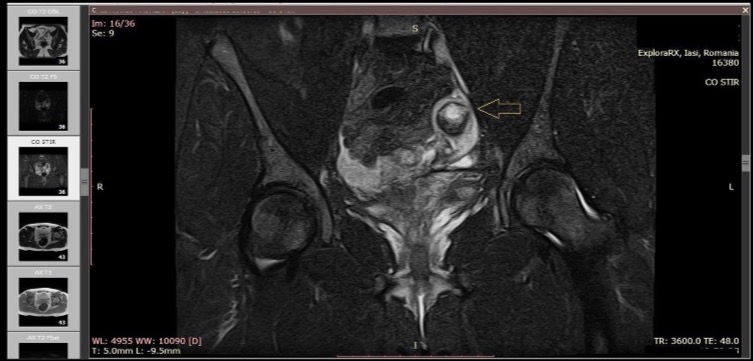

Figure 4. МРТ (режим STIR): эктопическая беременность в ампуле левой маточной трубы (стрелка) и остаточный фрагмент шейки матки в области влагалищного купола.